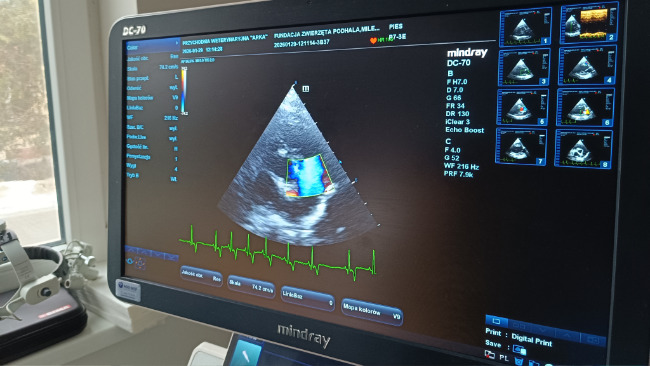

.... zmiany zwyrodnieniowe zastawki dwudzielnej. Płatki zastawki są zgrubiałe co powoduje niedomykalność zastawki i wtórne powiększenie jam serca.

Milenka ma chore serduszko, operacja nie wchodzi w grę. Co mogę zrobić? podawać jej leki i czekać mając pod ręką Furosemid.